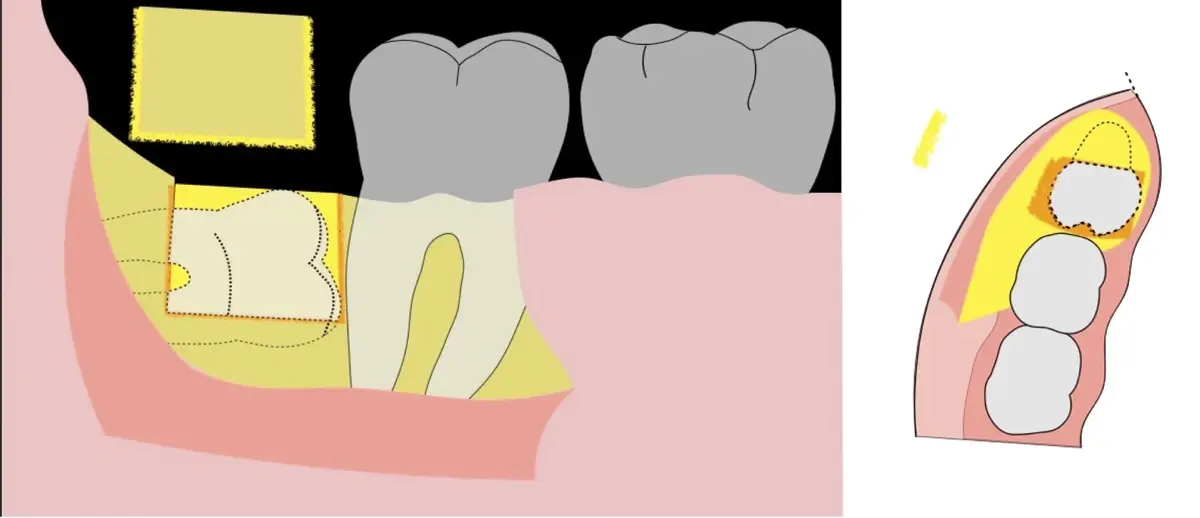

Para realizar la técnica de extracción de una tercera molar, una vez que se ha confirmado su diagnóstico, se debe considerar la posición del diente (vertical, mesioangular, distoangular, horizontal u otras), profundidad y grado de impacto, obstrucción a la erupción asociada a la segunda molar, morfología de la raíz (la curvatura de las raíces controla el camino de la exodoncia), relación con el canal del conducto dentario inferior, la patología asociada, la densidad ósea y la Integridad de la segunda molar.

En contraste, el instrumento piezoeléctrico utiliza un corte micrométrico que retira un área de superficie mínima de hueso, y reduce el riesgo de termonecrosis marginal en comparación con las fresas rotatorias convencionales.9 Los micromovimientos mejoran la precisión en el corte y el control táctil, y eliminan las macrovibraciones que se producen con los instrumentos rotatorios.10 Su frecuencia de oscilación es la amplitud de 60-200 μm horizontalmente y de 20-60 μm en sentido vertical, lo que es muy inferior en comparación con las micro sierras oscilantes; por lo tanto, proporciona cortes de osteotomía precisos y seguros. Adicionalmente, posee vibraciones ultrasónicas que descomponen el líquido de irrigación en partículas muy pequeñas (fenómeno de cavitación, que produce un efecto hemostático y así reduce la pérdida de sangre), lo que proporciona una visión clara y sin obstáculos del campo quirúrgico11,12.

El procedimiento se inicia colocando anestesia troncular para bloqueo del nervio dentario inferior y sus ramas. Luego, se establecerá el diseño de acceso según la disposición de la molar a extraer. Para fines didácticos, se explicará cómo se realizaría la extracción de la molar de la Figura 1: se realiza una incisión horizontal a nivel de la zona retromolar hasta llegar a distal de la segunda molar, continuándose con una incisión intrasurcular hasta mesial de la segunda molar, finalizando con una incisión vertical a espesor total hasta llegar a la línea mucogingival (Figura 2).